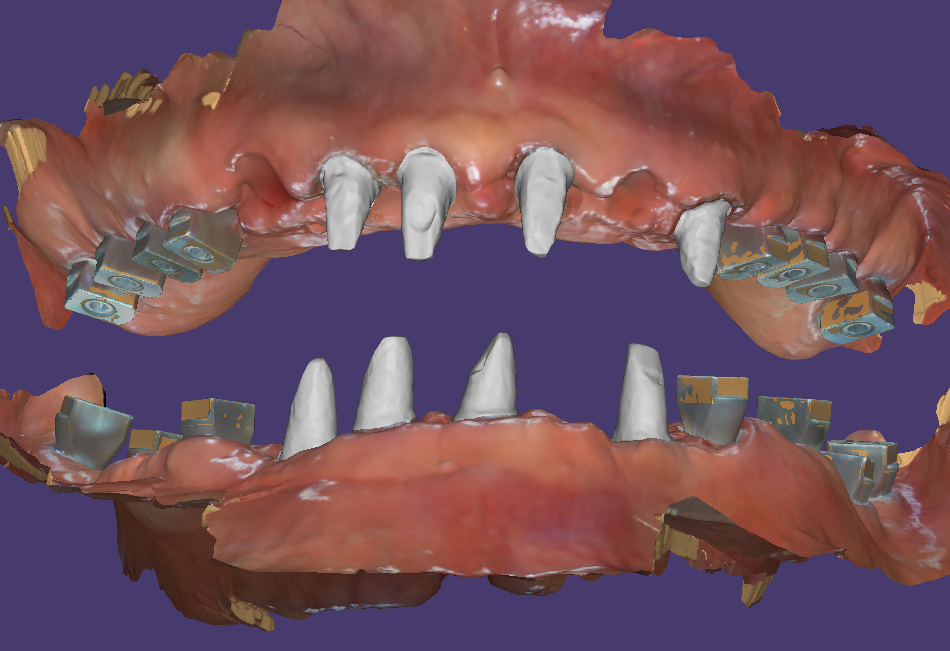

수술날 발치후 즉시식립 당일임시치아

흔들리는 모든 치아를 발치하고 염증을 제거한 다음 즉시식립을 시도했습니다. 위에는 12개, 아래는 11개의 임플란트를 식립했어요.

식립한 임플란트에 지대주를 연결해서 수술당일 임시치아를 만들었습니다. 임시치아를 디자인할 때 고경을 높여서 붕괴된 교합을 수정해 주었습니다.

전체임플란트에 적용하는 임시치아는 좌우의 모든 임플란트가 단단하게 서로 연결이 되어 있어야 합니다. 그래서 영상에서 보실 때에 따로 들어간 임시치아도 입 안에서 서로 연결하는 작업을 하게 됩니다.

그래야 임플란트들이 서로 의지하면서 힘을 상쇄시켜 줍니다. 그렇다고 하더라도 너무 강한 압력은 임플란트가 골융합을 할 때에 좋지 않습니다.